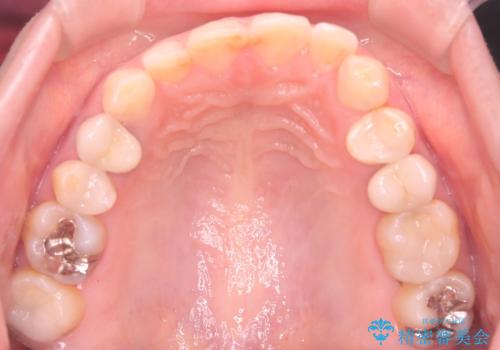

- 下の前歯のデコボコ(叢生)を気にされてご来院されました。精密な検査の結果、下の前歯を並べるスペースが不足していることが判明。患者様のご希望から、透明で目立ちにくい**インビザライン(マウスピース矯正)による治療計画を立案しました。主に歯の側面をわずかに削るIPR(歯間乳頭保護下ストリッピング)**などでスペースを確保し、下の前歯の叢生を解消することを目指します。

今回の矯正治療では、透明なマウスピース型の装置インビザラインを使用しました。目立たず、取り外しが可能なため、日常生活にほとんど影響なく治療を進めることができました。治療は、緻密に計算された計画に基づき、IPRなどで必要なスペースを確保しながら、下の前歯をスムーズに移動。これにより、長年の悩みであった下の前歯のデコボコが解消され、清掃しやすい、整った歯並びを獲得していただけました。